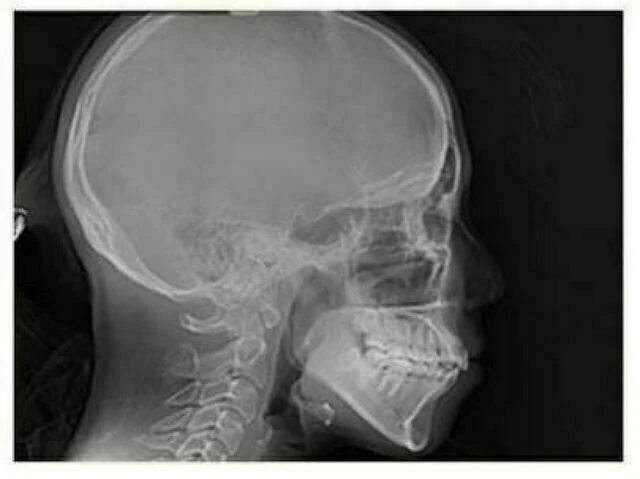

b. Phim sọ nghiêng: Cần cho MỌI trường hợp chỉnh nha. Không có ngoại lệ.